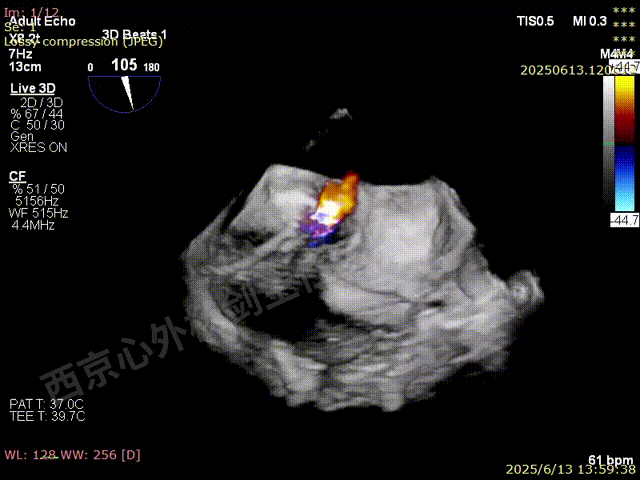

二尖瓣后叶栓系严重,前叶相对错位,反流束沿2区分布广泛,2偏3区处存在反流。

反流宽度至少23mm,因影像调整困难,考虑实际反流更宽。